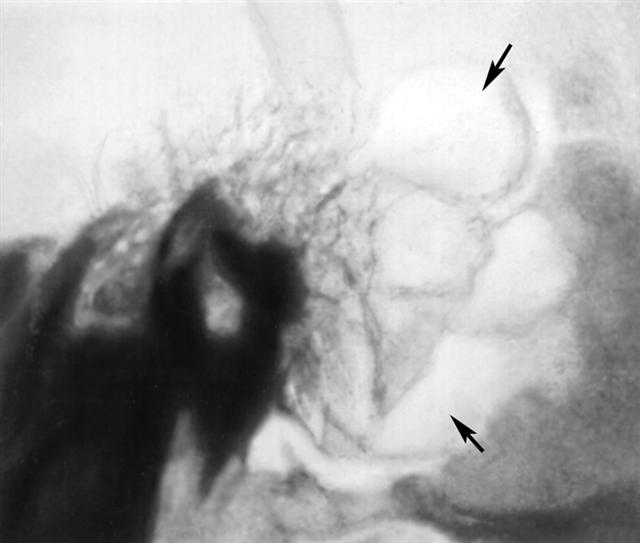

Рис. б). Рентгенограмма левой височной кости (боковая проекция) при гнойном мастоидите — на месте ячеистой структуры сосцевидного отростка виден очаг разрежения костной ткани (указан стрелками).